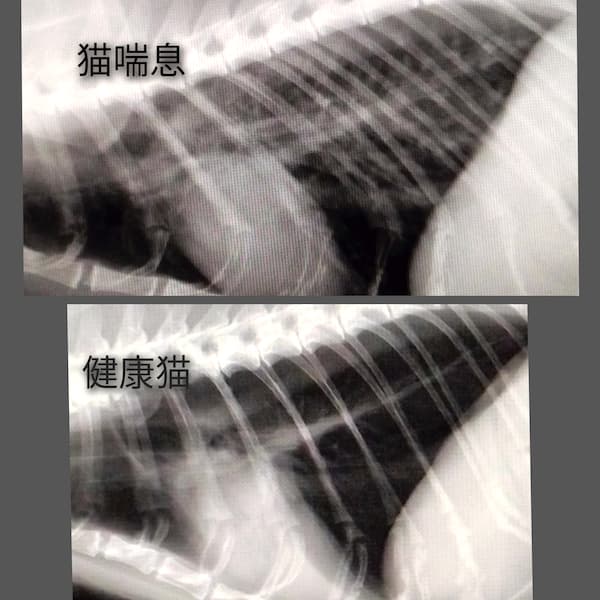

猫喘息(2025/07/14)

猫喘息は、何かしらの原因で気管支に慢性的な炎症があり、発咳、喘鳴(ゼーゼーという呼吸)、チアノーゼ等の呼吸障害を生じる疾患で、即時型アレルギーが関与しているとされています。胸部レントゲン検査、身体検査、血液検査などから総合的に診断します。治療には内服薬や注射薬の他、噴霧吸入療法(ネブライザー)や、飼育環境の整備などを行います。重症例では生涯に渡る治療が必要になることもあり、呼吸状態によっては命に関わる場合もあります。早期の治療介入により、重症化させないことが重要です。

獣医師 白石